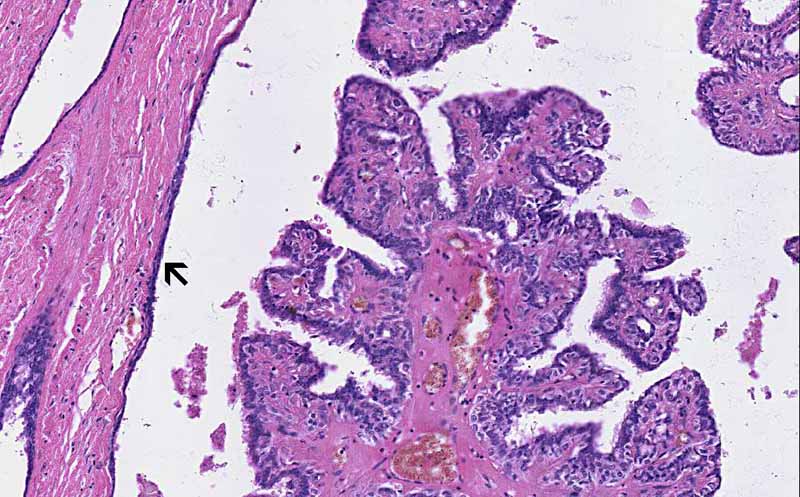

Area 1: The papilloma has dilated the duct. The dilated duct is lined by attenuated epithelial cells (arrow).

• The overall architecture is that of a papillary proliferation within a dilated cystic structure. The wall of the cyst is lined by attenuated epithelial cells (Area 1) which suggest that this is originally very likely to be a ductal structure.

• The papillary proliferation is composed of fronds of fibrovascular stroma covered by a single layer of epithelial cells without atypical nuclear changes or epithelial hyperplasia (piling up of layers of epithelial cells). The the epithelial cells have not breached the basement membrane and invade into the stroma. (Area 1 and 2)

• Intraductal papillomas often arise in the laciferous ducts in subareolar and central part of the breast. As illustrated here, the duct is dilated by the papilloma and may be dilated to a cystic extent. The cyst may contain clear fluid, bloody fluid, or even coagulated blood.